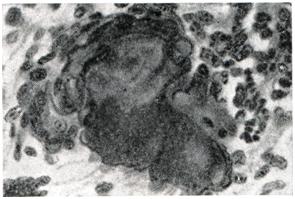

Рис. 2.

Актиномикотические друзы (крупные темные включения) среди гнойного экссудата (окраска по Шабадашу): 1 — малое увеличение; 2 — большое увеличение.

В срезах ткани встречаются друзы актиномицетов различных размеров (от 20 до 320 мкм). Они состоят из сплетения тонких нитей мицелия диаметром 0,4—0,7 мкм, имеют неравномерное, чаще дольчатое строение. Концы располагающихся радиально нитей мицелия представляются колбовидно утолщенными. В центре друзы обнаруживается иногда мицелий палочковидной формы без вздутия на концах. Считают, что друзы с «колбами» образует анаэробная форма актиномицета. Характерно, что в тяжелых по клиническому течению случаях «колбы», как правило, не образуются. Истинные актиномикотические друзы в срезах ткани необходимо дифференцировать от друзоподобных скоплений, образованных микробами и другими грибками. Это достигается, помимо окраски срезов ткани гематоксилинэозином, применением различных модификаций окрасок с генцианвиолетом, окраской по Цилю — Нельсену и применением PAS-реакции. Указанные методики позволяют обнаружить актиномицеты даже тогда, когда нити мицелия распадаются на отдельные короткие фрагменты.

Друзы актиномицетов чаще всего наблюдаются в центральных частях гранулем и окружены зоной лейкоцитарной инфильтрации. При отмирании гриба эта зона представляется более разреженной. Вокруг лейкоцитов, окруженных в свою очередь эпителиоидными клетками, можно нередко наблюдать гигантские клетки инородных тел.

Наряду с обнаружением друз необходимо оценивать их состояние, которое зависит от тканевой реакции. Изменение друз в ткани можно разделить на четыре группы: 1) лизис (выражается в краевом или тотальном растворении друз); 2) кальцификация друз; 3) поглощение друзы гигантскими клетками (рис. 3); 4) превращение друз в стекловидные аморфные массы. Фагоцитоз друз и явления лизиса свидетельствуют о повышении иммунных сил организма. Сопоставление тканевой реакции и состояния друз особенно важно при оценке эффективности применяемых методов лечения, когда речь идет о патоморфозе актиномикоза.